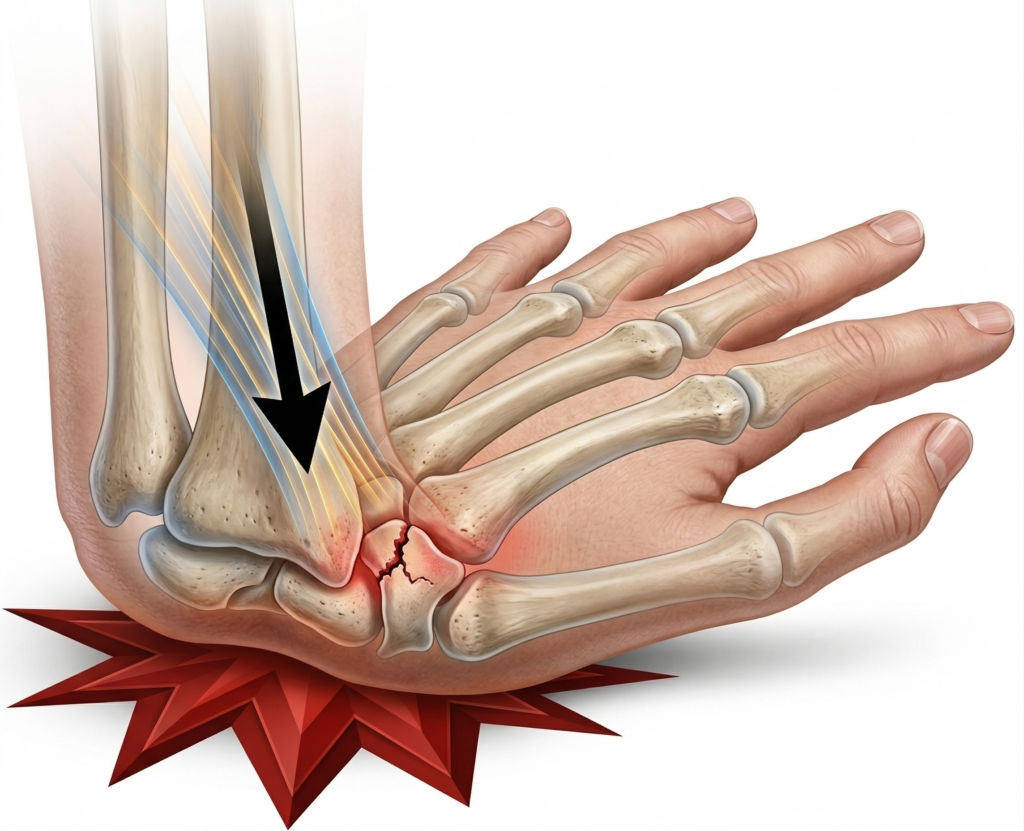

The most common cause is a fall onto an outstretched hand, where the wrist bends backwards as you try to break the fall.

This force is transmitted directly through the scaphoid.

The main reason we worry about scaphoid fractures is its unique blood supply.

- Most of the blood enters the bone from the distal (thumb) side

- It then travels back towards the proximal (wrist) side

If the bone is fractured, this blood supply can be disrupted—particularly in fractures closer to the wrist.